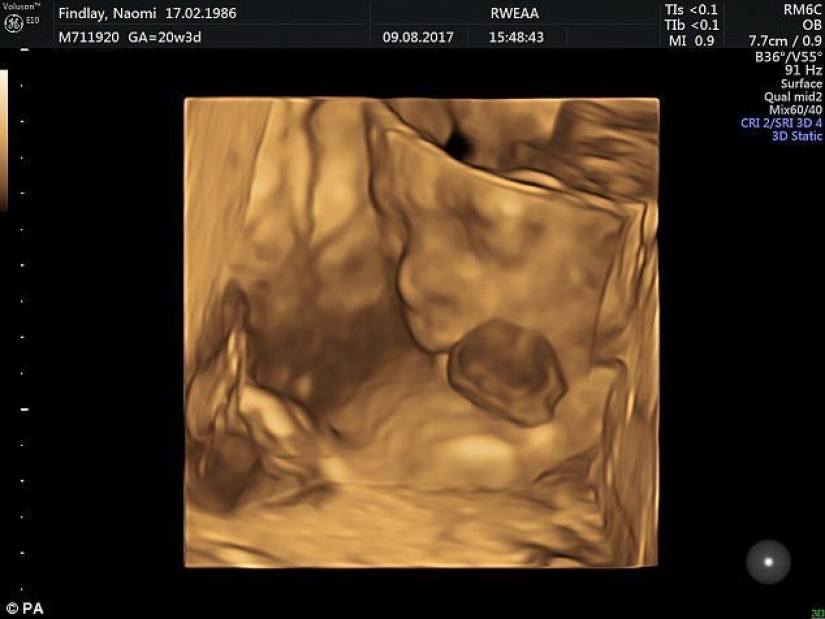

By Pictolic https://mail.pictolic.com/article/british-doctors-saved-a-baby-girl-who-was-born-with-her-heart-out.htmlLittle Vanillope Hope Wilkins was born with an extremely rare defect — ectopia of the heart. With this pathology, the human heart is located outside the body. Several dozen surgeons fought for her life, and to the joy of everyone, the girl survived!

The girl's parents found out about ectopia in the ninth week of pregnancy, but the mother refused to have an abortion, despite the persuasions of doctors.

According to the results of the tests, the baby had no chromosomal abnormalities. The specialists decided to direct all their efforts to save the child. Then a large team of obstetricians, neonatologists, cardiologists and other specialists was assembled.

According to statistics, more than 90% of newborns with ectopia of the heart are either born already dead, or die during the first days of life. This pathology is extremely rare — several cases per million. In practice, there is very little chance of surviving ectopia.